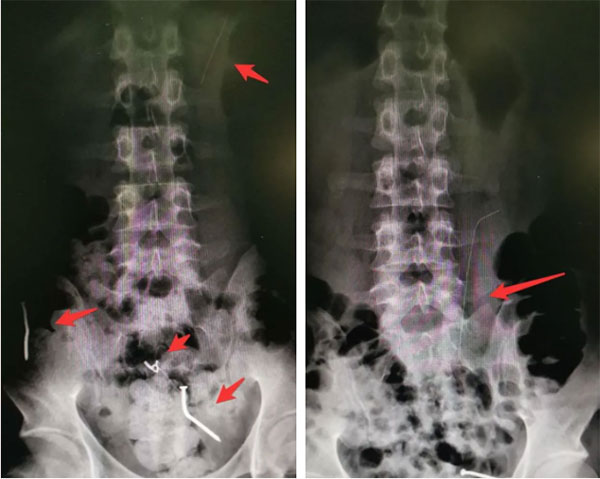

患者男,24歲,因“進食異物9天,腹痛1天”收住我院。行腹部立位平片見腹、盆腔可見4枚長短不一金屬異物,其中較短三枚異物位于盆腔,已自行由大腸排出體外;較長異物位于胃腔,為鐵絲,長約10cm,不能自行排出體外。經(jīng)脾胃病科(消化內(nèi)科)會診,在無痛麻醉狀態(tài)下,經(jīng)胃鏡成功取出胃腔內(nèi)異物。患者術(shù)后未發(fā)生消化道出血、穿孔等并發(fā)癥,恢復良好。

術(shù)前X片(紅色箭頭指向為金屬影)